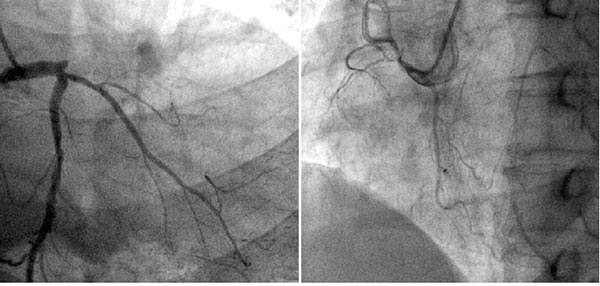

前臨床常用的冠狀動脈造影檢查包括冠狀動脈CT血管造影(CTA)和介入冠狀動脈造影兩種,都是評價動脈是否存在病變以及指導治療的重要手段,兩者各有優缺點,也各有利弊,在不同情況下選擇不同的檢查方式,需要根據情況來決定,不能一成不變的認為CTA好或者介入造影更好。

冠脈造影檢測